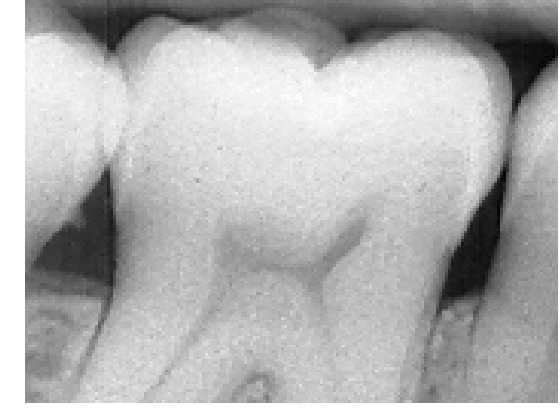

5.2.1 Multiclass high-quality bitewing X-ray image.

Refer to caption

Figure 9: Segmentation of inverse digitalized dental X-ray image that has a central molar tooth and partial views of its neighbor teeth, gums and background. First row, algorithms initialized with the modes of the histogram, fixed variance, second row, with automatic EM for Gaussian Mixtures. In both rows, from left to right, ML, ICM, GC and PCVT.

Our second scanned bitewing X-ray image shows a central molar tooth and partial views of its neighbor teeth, gums and background, Figure 9 (a). We have set three classes in this image to account for the differences between tooth enamel and dentin. Enamel is the thin, hard material that covers the dentin, or main body of the teeth, and protects it from harsh temperatures. We initialized both algorithms with automatic EM and supervised classification. In Figure 9 we can observe from the segmentations that, in the supervised case, (c), (d), (e), the teeth are correctly segmented, dentine is clearly differentiated from tooth nerve and enamel. Initializing with automatic EM, Figure 9 ((f), (g), (h), gives only a binary division, background from teeth and gum. In this example, PCVT makes a slightly better job than ICM, since the background is better separated from the teeth. The joint histogram of the image, Figure 9 (b), does show at least three distinctive modes; in Figure 10, the histogram shown in panel (a)corresponding to the X-ray image of an incisive, is flat. Its corresponding segmentations, shown in panels (c)-(f), made with four classes, do not distinguish well tooth enamel, dentin and background. In the expert’s opinion, PCVT is the only method that separates correctly enamel from background and dentin.